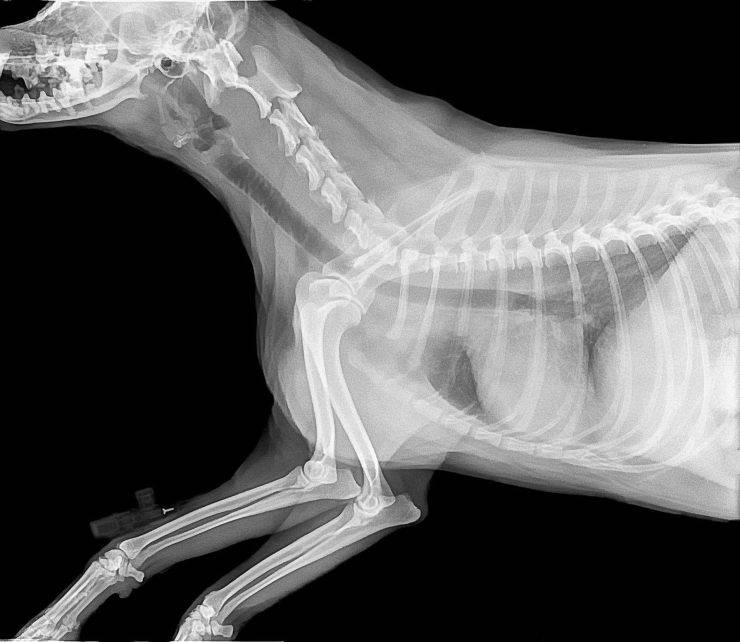

Inoltre, questa posizione delle gambe provoca dolori articolari e tramite l’utilizzo dei raggi X, si osserverà come le ossa non si adattano bene l’una all’altra e acquisiscono posizioni strane. In base alla gravità della situazione, possono anche presentare il torace piatto, che è stato deformato stesso dal peso del cane che è lasciato in costante contatto con il suolo, causando problemi respiratori.